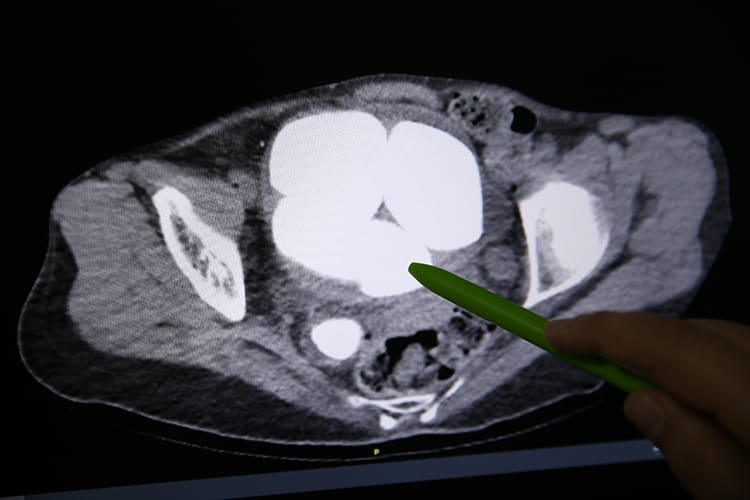

Şikayetlerin dayanılmaz noktaya gelmesi üzerine aile, bu kez Diyarbakır Gazi Yaşargil Eğitim ve Araştırma Hastanesi’nin yolunu tuttu. Üroloji Bölümünde Opr. Dr. Süleyman Çankaya tarafından yapılan tetkikler, yıllardır süregelen ihmali gözler önüne serdi. Yapılan tomografi sonucunda, hastanın mesanesinde ve idrar kanalında en küçüğü 2, en büyüğü ise 9 santimetreye ulaşmış toplam 6 taş tespit edildi. Taşların toplam ağırlığının yaklaşık yarım kilogramı bulduğu ve hastanın böbreklerine ciddi zararlar verdiği anlaşıldı.